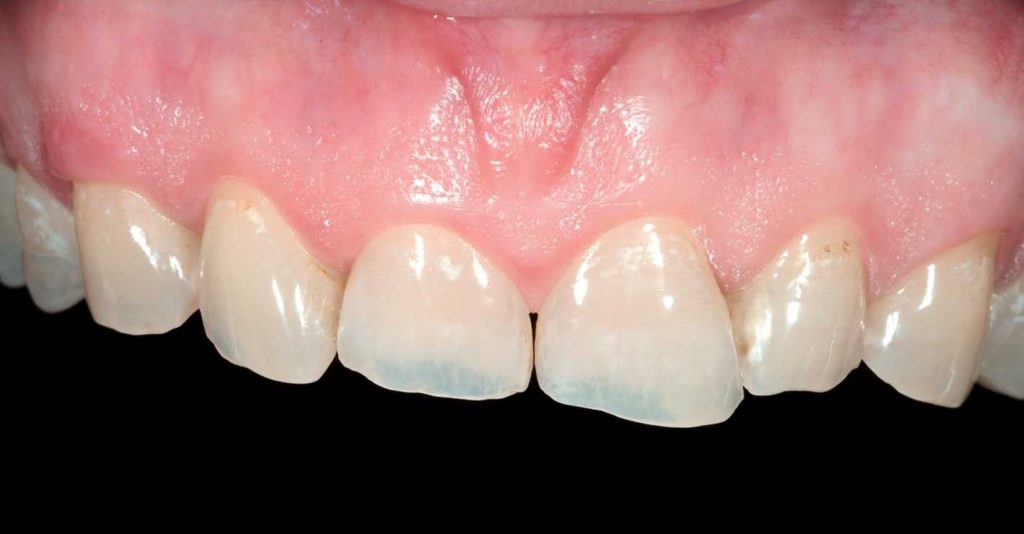

تصویر لمینت دندان روی لثه تحلیل رفته

آیا کامپوزیت یا لمینت برای دندان های دارای تحلیل لثه مجاز است؟

وقتی تحلیل لثه (Gingival Recession) اتفاق می افتد، بخشی از ریشه دندان نمایان می شود. این اتفاق باعث می شود دندان ها بلندتر از حالت طبیع...